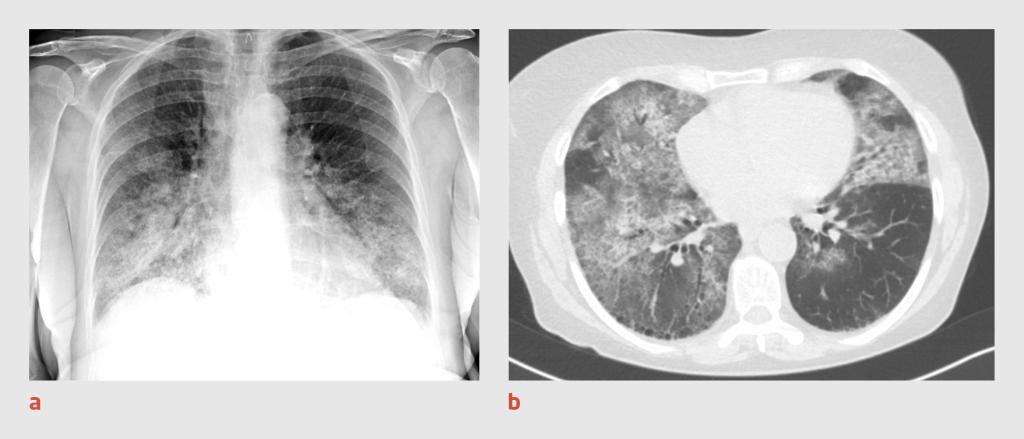

Figuur 2

Thoraxfoto en CT-thorax van patiënt B

Figuur 2 | Thoraxfoto en CT-thorax van patiënt B

(a) Thoraxfoto van een 82-jarige man waarop een ‘moppig’ beeld te zien is met perifeer gelegen consolidaties in beide longen. (b) Op de CT-scan van de thorax zijn in beide longen – met name in de bovenvelden – matglasafwijkingen en grillige consolidaties zichtbaar, overeenkomstig een CO-RADS-score van 4.

Er wordt een PCR-test verricht op SARS-CoV-2 in materiaal uit de nasofarynx en patiënt wordt intraveneus behandeld met ceftriaxon 2 g 1 dd. De volgende dag blijkt de uitslag van de PCR-test negatief te zijn. Omdat wij op basis van het klinische beeld nog steeds een sterk vermoeden van covid-19 hebben, wordt CT-onderzoek van de thorax verricht. Op de CT-scan worden in beide longen – met name in de bovenvelden – matglasafwijkingen en grillige consolidaties gezien (CO-RADS-score 4) (figuur 2b). De isolatiemaatregelen blijven gehandhaafd en er wordt nog tweemaal een PCR-test verricht, waarvan de uitslag beide keren negatief is.